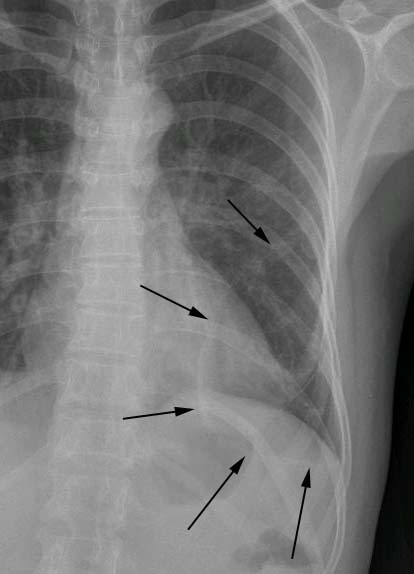

标题: X2653:女,50岁,咳嗽,发热,38度,

除有肺部感染,看看箭头所示,病人随后加照左侧位,显示不好,又照了斜位,还有ct.

左下肺斑片状高密度影,与脊柱重叠,边缘模糊,正位看肺门不大。侧位看似有肿块。考虑炎症。ct待排占位。

左中、下肺野见斑片状密度增高影,边缘较模糊,左肺门影增大,侧位呈块状。

考虑:1、左肺感染性病变,建议治疗后复查。

2、左侧占位性病变,建议作ct检查。